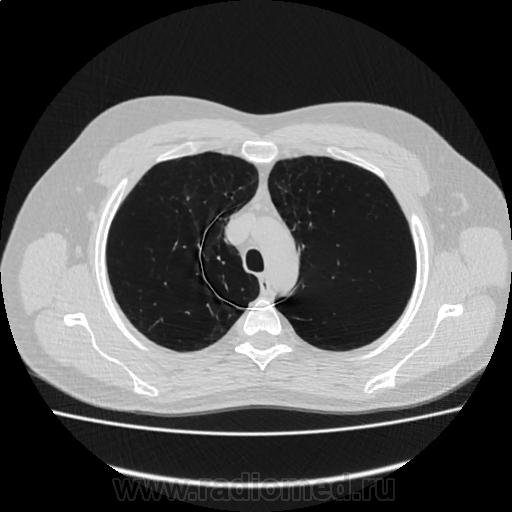

Заранее прошу прощение за некачественные рентгенограммы, так как фотографировал с пленки на телефон. А на КТ-исследовании артефакты, так как, как раз перед обследованием данного больного произошел выход из строя какой то платы.

назначен день КТ, как я уже говорил прям пред обследованием пациента полетела какая то плата, появились артефакты, но явность картины не скрыть!):

написали панлобулярная эмфизема преимущественно в верхних долях. мне кажется это  говорит о врожденной верхнедолевой эмфиземе

Похоже, что мало сосудов для просто эмфиземы, практически все сосуды вверху исходят из средних отделов.  Нет ли пороков развития сосудов легких, хорошо бы контрастирование или узи сердца.

Чисто субективно корни представляются гипопластичными в области головок и частично тел.